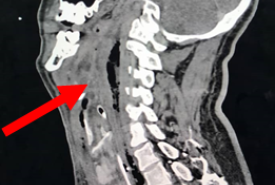

Retropharyngeal Abscess with a Missed Migrating Foreign Body: A Case Report